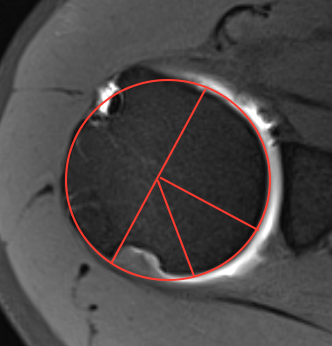

Best fit circle measurement

Best fit circle over inferior glenoid

- perpendicular line through center of circle

- measure percentage bone loss

10 - 15% defect

20 - 25% defect